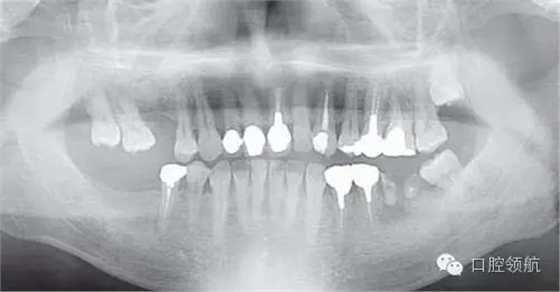

患者,38歲,男性,作為需要全面治療的患者來院?;局委熀螅蚁骂M磨牙區(qū)及右上頜磨牙區(qū),還有拔牙后的左下頜磨牙缺損區(qū),擬進行種植修復。圖1為初診時的曲面斷層影像,問診,模型診斷,曲面斷層檢查均未見異常,因此,最先在右下頜磨牙缺損區(qū),繼而在右上頜磨牙缺損區(qū)植入種植體,這些種植體愈合良好。

圖1 初診時的曲面斷層影像。